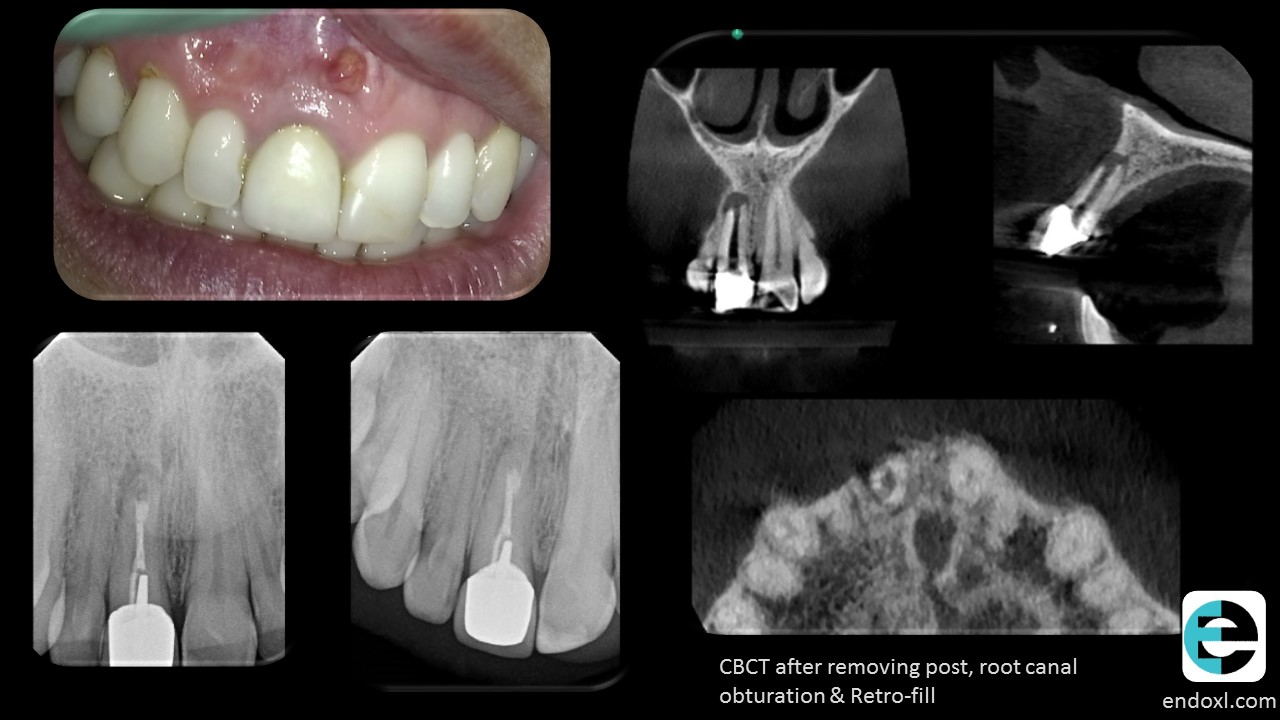

Patient presented with a sinus tract -buccal of tooth # 8

History of initial root canal 36 years prior and PA surgery with MTA fill and without retreatment by an endodontist 5 years prior.

Orthograde Retreatment – removing the hardware: pre-fab metal post, gp, MTA and software – cotton fibers, Placed white MTA apical plug after resolution of sinus tract.

2 year recall CBCT